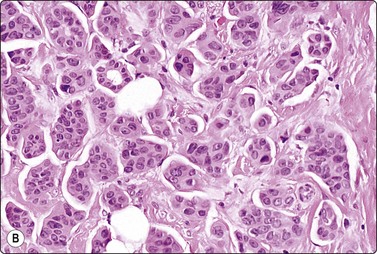

A comparison between the basic benign pattern (non-neoplastic glandular tissue) and the most common malignant pattern (low-grade carcinoma of no special type) in FNB of breast lesions is given in Table 7.2 (Figs 7.2-7.4).

Table 7.2 Comparison of the benign pattern and low-grade carcinoma in FNB smears

Non-neoplastic breast tissue (Figs 7.2A, 7.3A and 7.4A) Low-grade carcinoma NOS (Figs 7.2B, 7.3B and 7.4B)

1. Overall low cell yield 1. Variable but higher cell yield

2. Sheets and aggregates of cohesive, small, uniform cells 2. Irregular clusters of less cohesive, small, mildly irregular cells

3. Small rounded nuclei, bland chromatin, some overlapping 3. Slightly larger and darker nuclei, relatively bland chromatin

4. Myoepithelial cell nuclei among epithelial cells 4. Myoepithelial cell nuclei not seen

5. Variable numbers of single, bare, bipolar nuclei scattered in the background 5. Single cells, most with some cytoplasm, identical to those forming clusters; no bare bipolar nuclei

image image

Fig. 7.2 Non-neoplastic glandular breast tissue and low-grade duct carcinoma

Low-power view; (A) Bimodal population of epithelial sheets and single bipolar nuclei of non-neoplastic glandular breast tissue; (B) Single population of epithelial cells in low-grade carcinoma (MGG, LP).

Fig. 7.3 Non-neoplastic glandular breast tissue and low-grade duct carcinoma

High-power view, air-dried smears; (A) Non-neoplastic glandular breast tissue; (B) Low-grade duct carcinoma. Note single bipolar nuclei in A, and absence of bipolar nuclei, relatively mild nuclear atypia and some loss of cohesion of malignant cells in B (MGG, HP).

Fig. 7.4 Non-neoplastic glandular breast tissue and low-grade duct carcinoma

High-power view, Pap-stained smears; (A) Bimodal population in smear from non-neoplastic breast; (B) Single and clustered cells in low-grade carcinoma; some single cells probably stromal (Pap, HP).

The basic benign pattern is common to normal glandular breast tissue. Variations occur with the menstrual cycle and with the age of the patient, depending upon the variable proportions between epithelial cells and fibrous stroma. The yield of the needle biopsy is usually scanty and multiple biopsies should always be made to increase the likelihood that the material is representative.

The bimodal pattern of cohesive groups of epithelial cells and scattered single, bare, oval/bipolar nuclei is diagnostic of benign, non-neoplastic breast tissue. Ductular epithelial cells – this term is used here to designate cells from the intralobular epithelial structures of the resting breast, which differ distinctly from the acinar epithelial cells seen in pregnancy and lactation (see below) – are cohesive and are seen as small epithelial groups, which represent terminal ductules. The cohesiveness of non-neoplastic epithelium is in contrast to the dyscohesion of malignant cells unless very well differentiated (Figs 7.3 and 7.5). The nuclei are irregularly distributed within the groups and may appear crowded and overlapping (multilayered). They are uniform, small, round or oval, dark, with a granular chromatin. Nucleoli are indistinct or are very small. Cytoplasm is scanty, visible, but without distinct cell borders; it is pale and may show a blue granulation (MGG). Epithelial fragments from larger ducts are sometimes present. They form monolayered sheets of regularly arranged, slightly larger cells with uniform nuclei. The single, bare nuclei scattered in the background are of the same size or a little smaller than those of the epithelial cells. They have a bipolar/oval shape and a very smooth nuclear outline. The chromatin is dense and homogeneous and nucleoli are not seen (Figs 7.3A and 7.4A). The bipolar/oval nuclei sometimes wash off in heavily bloodstained and in wet-fixed smears. Nuclei of similar appearance can also be seen scattered between the cells of the epithelial fragments, distinguishable from these by their smaller size, bipolar shape, and darker staining (Fig. 7.6). They no doubt represent myoepithelial cells, whereas the single nuclei scattered in the background may be either myoepithelial or derived from the specialized, intralobular connective tissue. The number of bipolar/oval nuclei in smears corresponds closely to the cellularity of the lobular stromal component in sections. This is particularly evident in smears from fibroadenoma. However, a recent study of p63 immunoexpression in these cells concluded that the majority was of myoepithelial origin.91 Small fragments of collagen may be seen, particularly if larger-caliber needles have been used, but are usually inconspicuous, whereas fragments of adipose tissue are frequently present.